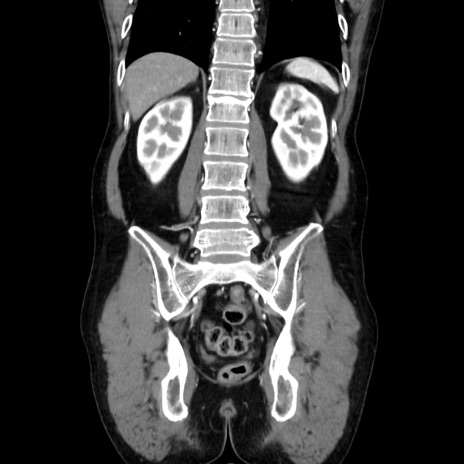

症例37(冠状断像)

【症例】40歳代 男性

【主訴】腹痛

【現病歴】4時間ほど前に電車に乗車中に臍部上より腹痛出現。徐々に増悪し起立困難となり、救急外来受診。生ものは数日食べていない。今朝お雑煮を食べた。

【身体所見】BT 36.8℃、BP 117/84mmHg、HR 91/min、SpO2 97%、苦悶様、腹部:臍上部広範囲圧痛あり、反跳痛±

【データ】WBC 8100、CRP 0.03